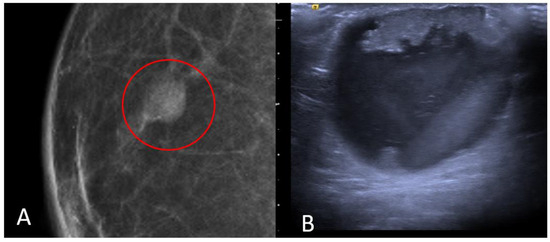

The most common histological subtype of primary malignant breast lesions in men is invasive ductal carcinoma (IDC) [27,28], shown in Figure 7.

Figure 7.

A 60-year-old man with gynecomastia presenting a retroareolar lump on the right breast with nipple retraction and without nipple discharge. Histological examination revealed an invasive ductal carcinoma (ER + 90%, PR + 60%, HER2 score 1+). Ultrasound examination (A) shows a hypoechoic irregular mass (white arrow) in the retroareolar region, with lobulated margins. A mammography (B) shows an irregular hyperdense retroareolar mass with lobulated margins (red circle).

IDC typically originates from the terminal duct–lobular unit [28,29]. Clinical features include a palpable unilateral retroareolar mass with nipple retraction and skin thickening [28,29]. Around 25% of cases may present with bloody nipple discharge [28]. IDC can be associated with ductal in situ components in up to 50% of cases [30]. Mammographically, IDC appears as a retroareolar irregular high-density mass with spiculated or micro-lobulated margins [30,31]. Unlike in women, IDC in men is rarely associated with microcalcifications due to the involution of the ductal system caused by the absence of estrogen and progesterone stimulation [28,29]. Ultrasonography reveals solid, hypoechoic, and irregular masses with margins ranging from microlobulated to spiculated [32]. Papillary carcinoma (PC) is the second most common invasive subtype of MBC and has a higher incidence in men compared to women [33]. PC is characterized by neoplastic proliferation of cells with fibrovascular stalks lacking an intact myoepithelial cell layer [34]. It typically presents with bloody nipple discharge and occurs in the subareolar region. Mammographically, PC may exhibit well-circumscribed or spiculated margins, while ultrasound imaging may reveal a dilated duct or cyst, often appearing as a complex cyst with solid papillary projections along the cyst wall [35,36] (Figure 8).